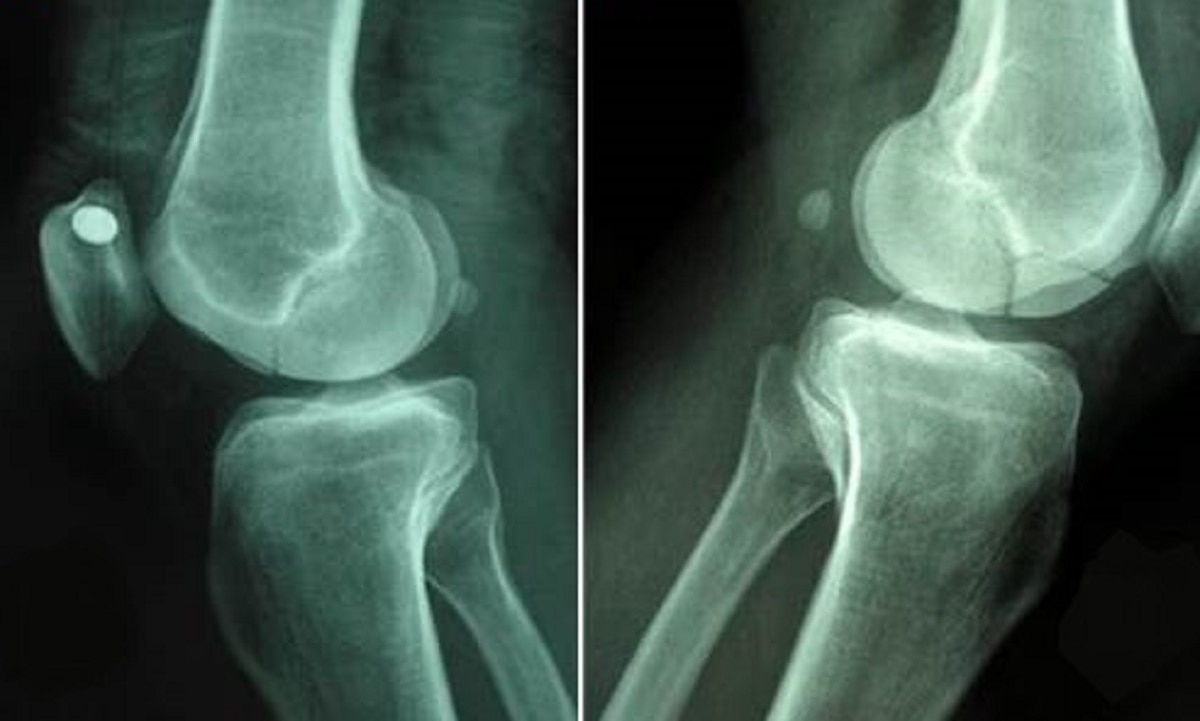

स्टडी में शोधकर्ताओं ने पाया कि वेजिटेरियन लोगों में फ्रैक्चर होने (हड्डी टूटना) का खतरा मांस खाने वालों की तुलना में 9 प्रतिशत ज्यादा था. वीगन डाइट फॉलो करने वालों के लिए तो समस्या और भी बड़ी निकली. वीगन डाइट फॉलो करने वालों में हड्डी टूटने का खतरा 43 प्रतिशत ज्यादा था.

शाकाहारी और मछली खाने वालों में हिप फ्रैक्चर का खतरा लगभग 25 प्रतिशत बढ़ गया था. शाकाहारी लोगों में हिप फ्रैक्चर की समस्या मांस खाने वालों के मुकाबले दोगुनी हो चुकी थी. जबकि वीगन लोगों (डेयरी प्रोडक्ट भी ना खाने वाले) में मांस खाने वालों की तुलना में पैर में फ्रैक्चर की दिक्कत 81 प्रतिशत ज्यादा पाई गई.